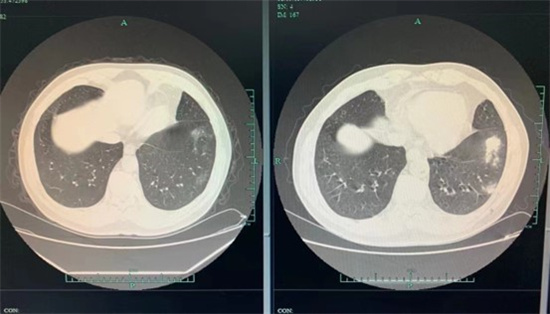

(患者3个月前、后ct对比)

还好发现及时,只是轻度炎症,张大爷回家以后按照医嘱服用抗真菌药物,不再去西湖喂鸽子。经过3个月的治疗,张大爷再回到金医生门诊复查时,肺结节明显变小了,一家人这才松了口气。